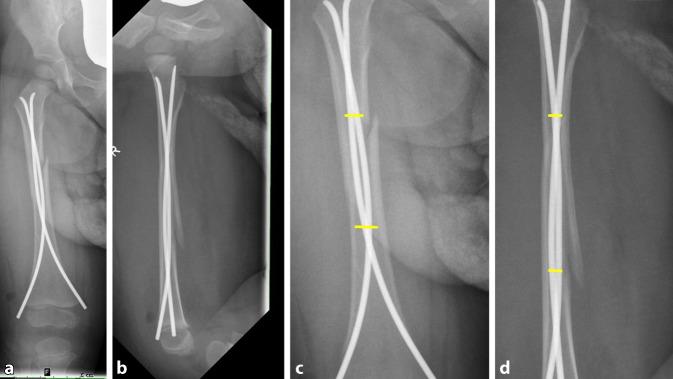

Conservative treatment was carried out in 19% of the cases. Among the surgical procedures the ESIN technique was predominant (n = 60). Complications that needed revision occurred in 10% of the children after conservative treatment. Revision surgery had to be carried out in more than 6% of the cases in children who were surgically treated. Among the surgical procedures ESIN stabilization demonstrated the lowest revision rate with only 3%. Children under three years and adolescents had a higher risk for developing complications. If the ESIN wires used were too thin in relation to the diameter of the medullary cavity there was an increased probability of complications of around 30%.

19%的病例采用保守治疗。在手术治疗中,ESIN技术占主导地位(n = 60)。保守治疗后,10%的儿童出现需要翻修的并发症。接受手术治疗的儿童中,超过6%的病例需要进行翻修手术。在手术治疗中,ESIN固定术的翻修率最低,仅为3%。3岁以下儿童和青少年发生并发症的风险较高。如果使用的ESIN钢丝相对于髓腔直径过细,并发症的发生率会增加约30%。